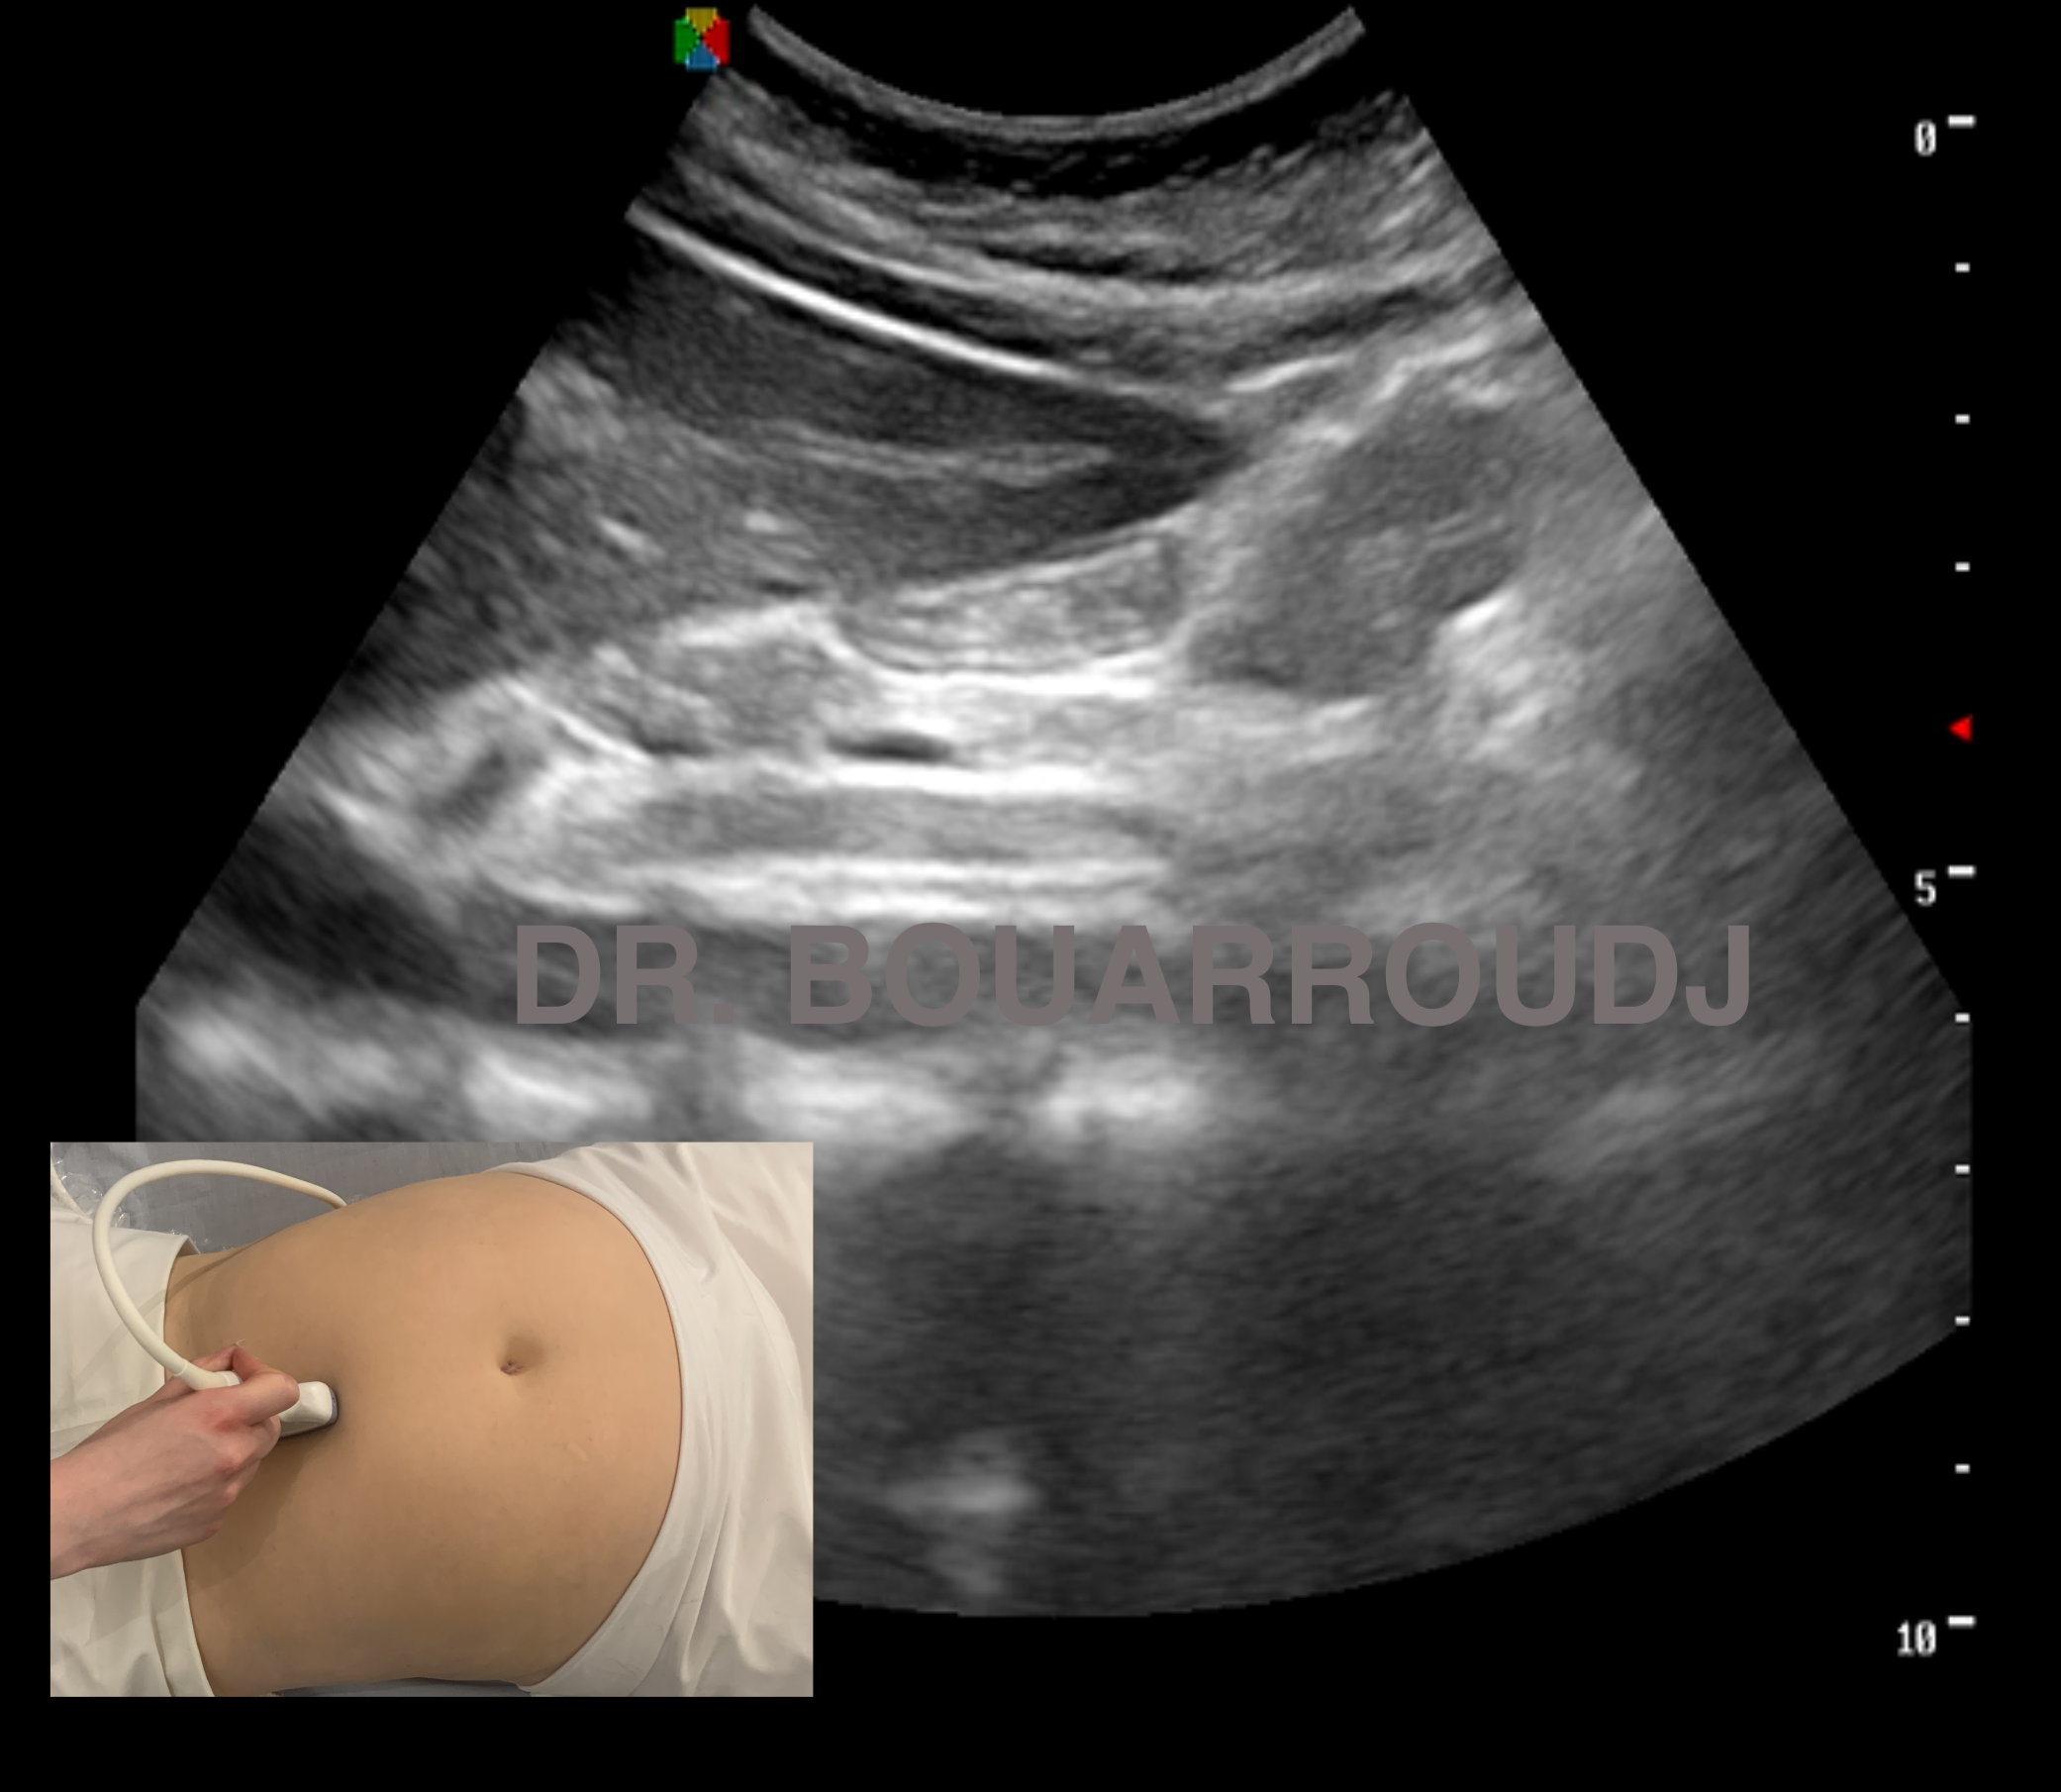

L’American Society of Anesthesia (ASA) a récemment émis une recommandation majeure concernant la gestion péri-opératoire des patients sous agonistes des récepteurs du GLP-1, tels que l’Ozempic. Les agonistes du GLP-1 sont utilisés chez le sujet diabétique type 2 mais aussi prescrits pour la perte de poids en raison de leur capacité à retarder la vidange gastrique et à réduire l’appétit. Ces medicaments retardent donc la vidange gastrique chez des sujets qui possèdent deja un haut risque d’inhalation (diabétiques et obèses). Les premiers rapports (1), (2) ont montré que les patients qui ont subi des effets secondaires gastro-intestinaux, tels que des nausées ou des vomissements, pendant qu’ils prenaient des agonistes du GLP-1 étaient plus susceptibles d’avoir un contenu gastrique résiduel plus important. Le risque d’aspiration pulmonaire et de syndrome de Mendhelson est donc réel. Pour cela L’ASA a émis des recommandations notamment la réalisation d’une échographie gastrique pour l’évaluation du contenu chez des patients qui sont toujours sous agoniste du GLP-1. Il faut rappeler que la molécule de l’Ozempic est prescrite toutes les semaines. Il est recommandé donc pour une chirurgie réglée d’arrêter cette médication une semaine avant (3). Dans le cas contraire et particulièrement chez les malades présentant des troubles Gastro-intestinaux qui sont susceptibles d’avoir un continu gastrique résiduel, une échographie gastrique est indiquée à fin d’évaluer le contenu gastrique.Le POCUS Point Of Care Ultrasound commence a entrer dans les moeurs de la pratique anesthésique.En 2020 ,dans un article en ligne publié sur ce site et intitulé L’Échographie en Urgence et POCUS : Point of Care Ultrasound j’ai insisté sur ce qu’il convient d’appeler le POCUS gastrique.En 2015-2016 a Lyon j’ai été initié a cette technique par les Dr Bouvet et Boselli lors du DU d’Anesthesie Regionale.A l’époque beaucoup d’encre a coulé.

-Si le patient ne présente aucun symptôme gastro-intestinal, mais que les agonistes du GLP-1 n’ont pas été arrêtes, prendre des précautions en supposant que le patient présente un « estomac plein » ou envisager de recourir à l’échographie pour évaluer le contenu de l’estomac. Si l’estomac est vide, procédez comme d’habitude. Si l’estomac est plein ou si l’échographie gastrique n’est pas concluante ou n’est pas possible, envisagez de retarder l’intervention ou de prendre les précautions nécessaires en cas d’estomac plein. Discuter du risque potentiel de régurgitation et d’aspiration du contenu gastrique avec le chirurgien et le patient.

La recommandation de l’échographie gastrique péri-opératoire par l’ASA pour les patients sous agonistes du GLP-1 marque une avancée importante dans la prise en charge préopératoire et le recours au POCUS gastrique. En identifiant les cas présentant un contenu gastrique résiduel élevé, les professionnels de santé peuvent désormais avoir recours a aux ultrasons afin de réduire les risques de complications et d’aspiration pulmonaire.Lors des Masterclass POCUS cette technique est enseignée systématiquement depuis 2017…..Un avenir prometteur pour l’échographie gastrique.